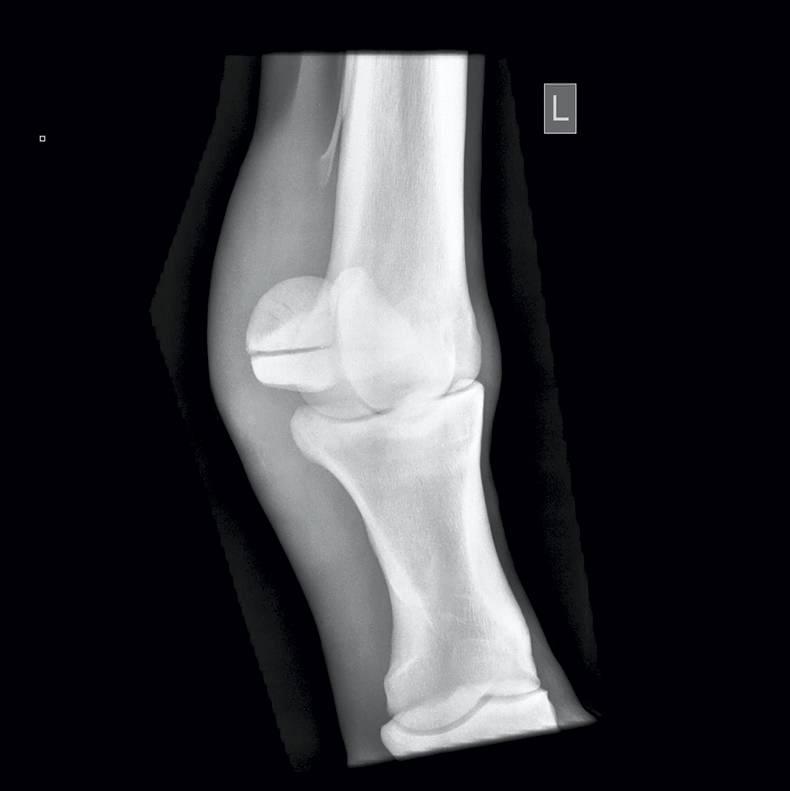

WITH the sales season in full swing, a set of X-rays of a horse involves usually a standard set of 36 views of the fetlocks, knees, hocks and stifles.

A huge number of abnormalities can be found on X-rays, such as sagittal ridge Osteochondritis Dissecans (OCD) defects in the front fetlocks; fragments off the back of the pastern bone; bone cysts in the ulnar carpal bone; and ‘spurring’ in the hock joints.